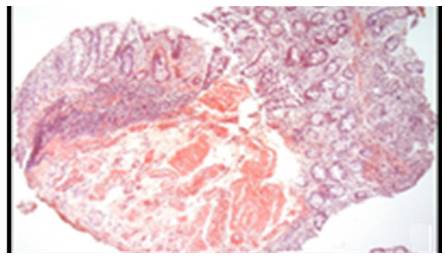

AL amyloidosis was confirmed by perianal lesion and colonic mucosa biopsy (Figures 7, 8, 9 and 10), where a deposit of eosinophilic amorphous material was found in the submucosa and vessel wall with the typical apple-green birefringence of Congo Red stained preparations under polarized light and confirmed with immunohistochemistry. Renal biopsy showed tubulopathy due to lambda free chain deposits, along with amyloid deposits in arterioles.